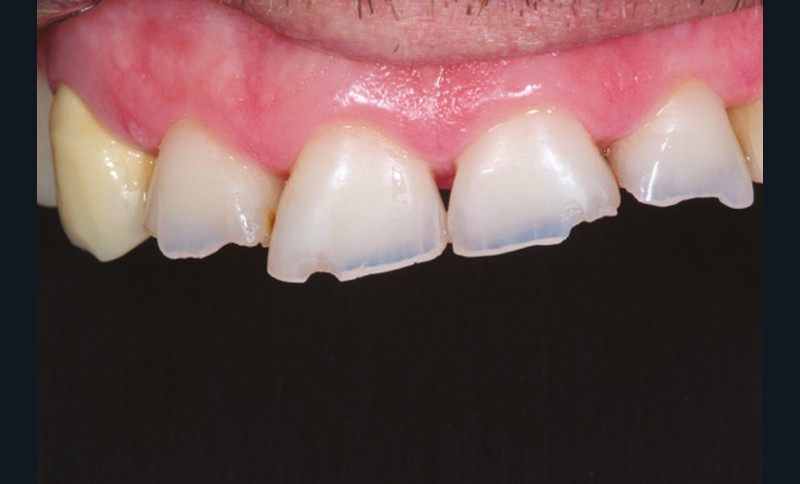

Le principe de protection mutuelle implique que les dents postérieures protègent les antérieures lors de la mastication. Des extractions non compensées de molaires, par exemple, entraîneront une hypersollicitation des antérieures et une usure importante du fait du principe de calage ainsi qu’un risque de perte de dimension verticale (fig. 10 à 13).